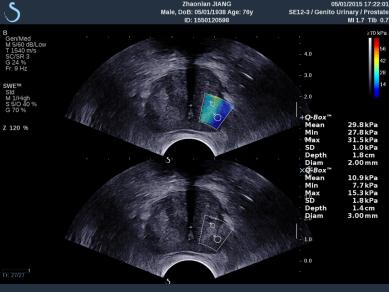

E成像(SWE)實時剪切波彈性成像技術(shù)

“聲藍”獨有的E成像(SWE)實時剪切波彈性成像技術(shù)可以廣泛應(yīng)用在實性臟器腫瘤的早期檢出和鑒別診斷、定量評估、介入穿刺引導(dǎo)、各類疾病治療前后的評價等,也是唯一全面通過美國FDA認證的實時、全幅、全定量的組織硬度可視化測量模式,因而為臨床診斷和治療,提供了安全、無創(chuàng)、有效的最新影像學全新檢查方法。目前已被應(yīng)用于甲狀腺、乳腺、肝臟、腎臟、前列腺、腸管、淋巴結(jié)、肌肉骨骼、軟組織等全身器官的鑒別診斷和定量評估。

彈性超聲與以往普超聲相比,相當于“深觸診”,可以更加直觀地“接觸到”軟組織的形態(tài),并且速度可達到1厘米/秒。與此同時,它的畫面是連續(xù)性的,具有以往單點式的超聲設(shè)備無可比擬的優(yōu)勢。它的“彈性”級別也是最高的,特別適應(yīng)于甲狀腺和乳腺的超聲診斷,并且配備了多個探頭,適用于人體不同部位的超聲需求。彈性超聲的引進與應(yīng)用,可對腫瘤的良惡性鑒別診斷及肝纖維化的無創(chuàng)診斷提供重要依據(jù),可明顯提高診斷準確率,具有非常高的敏感性、特異性,提高檢出率,為臨床診斷及治療提供重要依據(jù),盡早為患者爭取最佳的治療時機。